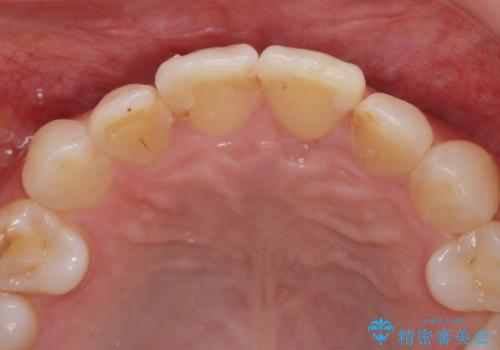

- う蝕治療や矯正治療を終えた患者様です。

歯ぎしりや歯の保護のためにナイトガードを作製しました。